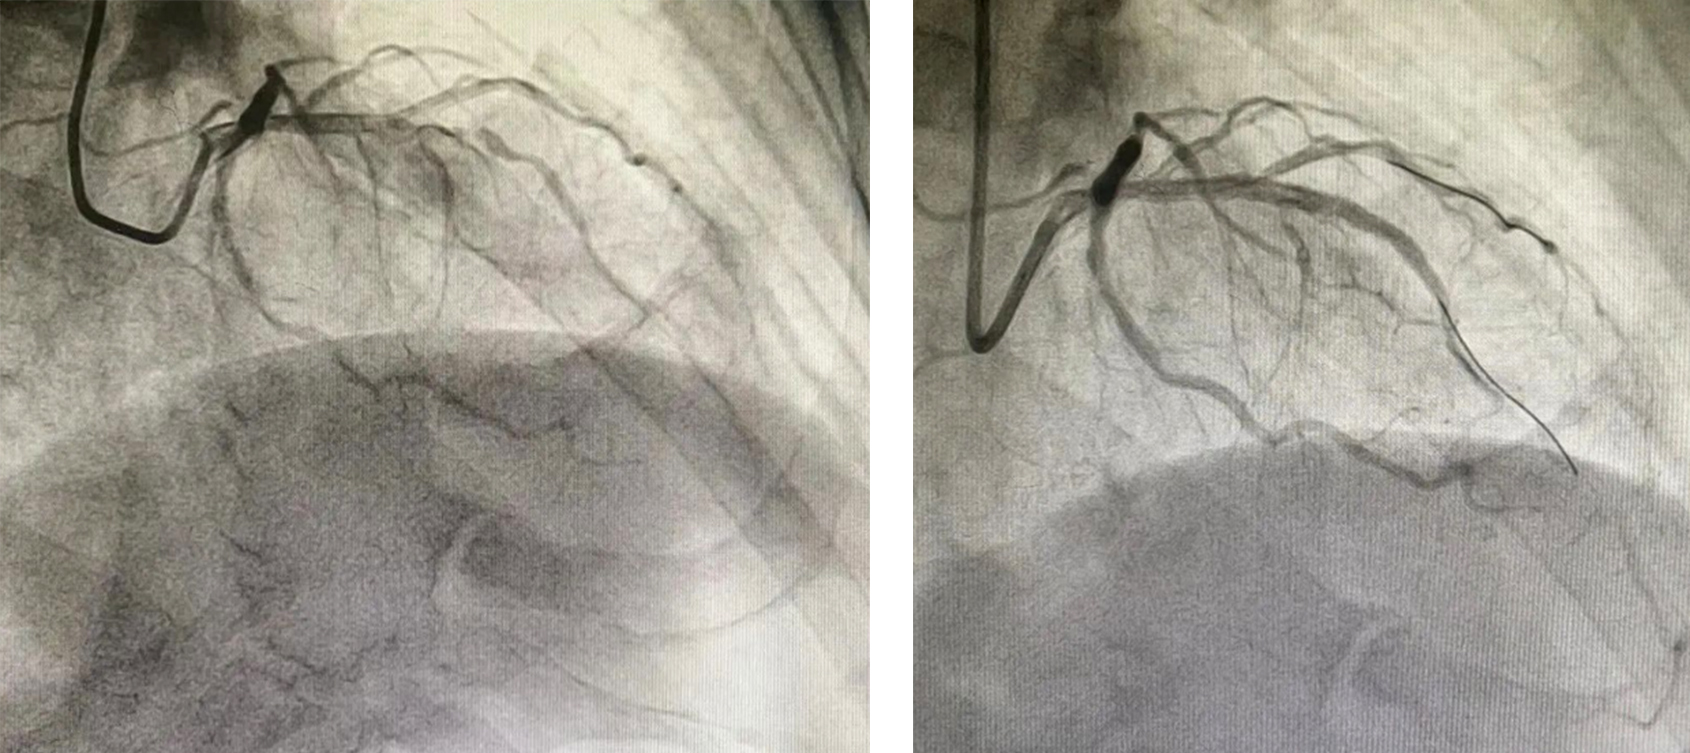

患者男性,81岁,10月17日活动时突发胸闷、胸痛,伴大汗淋漓,急诊就诊后查心电图提示急性前壁心肌梗死,兰大二院帮扶队员马如超查看患者情况后决定立刻开通绿色通道行急诊手术。术中造影见冠状动脉前降支次全闭塞,马如超带领心内科介入团队行急诊PCI术,术中植入支架1枚,并制定详细的治疗方案,术后经过精心诊疗后患者已康复出院。